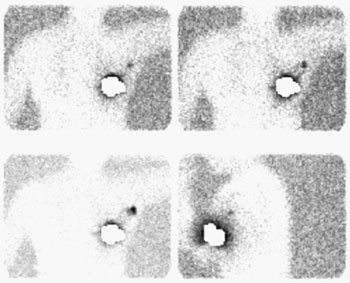

Sentinel lymph node imaging: The lymphoscintigraphy exam below was performed using a peri-tumoral tracer injection. Images were performed at 5, 10, and 15 minutes after injection in a LAO projection with the left arm behind the patient's head. A lead shield was placed over the breast. The exam demonstrated rapid localization of the primary lymphatic drainage to the axilla. Following the procedure the patient went to the operating room for gamma probe localization of the sentinel node. |